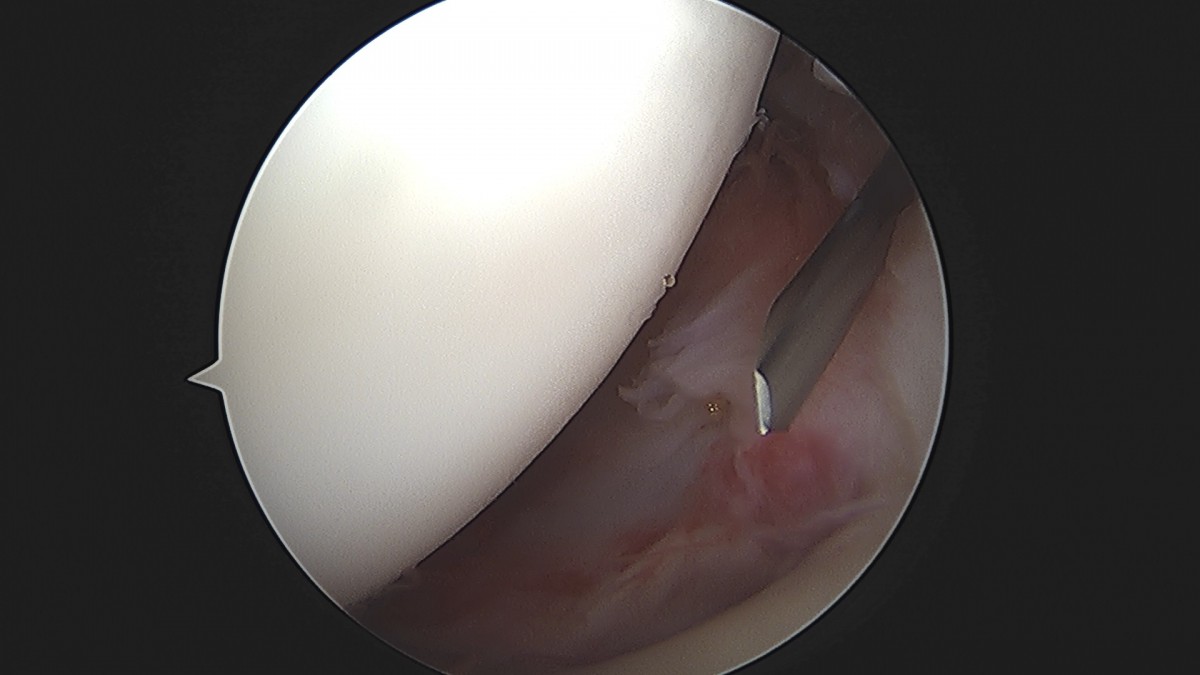

이재상원장님 어깨 견봉하 감압술 및 관절낭 이완술 주혜O 환자

dae765e4d9ac96aee867c9d6292d8784_1758003914_0014.jpg